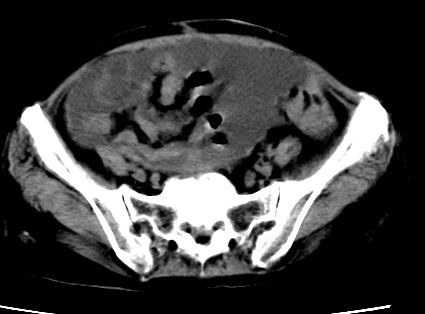

标题: CT23975:女61岁,腹部不适,明显消瘦 [打印本页]

标题: CT23975:女61岁,腹部不适,明显消瘦

既往5年前卵巢癌行子宫及附件切除,右乳癌术后一年,考虑腹膜转移?

大量腹水,考虑腹膜转移。肝脏低密度灶。1囊肿,2转移。

1)结合病史,考虑腹膜及网膜转移瘤。2)肝脏多发性低密度灶,不排除转移瘤。3)大量腹水。

考虑卵巢癌行子宫术后复发,并肝、腹腔 、大网膜转移可能性大。

大量腹水。